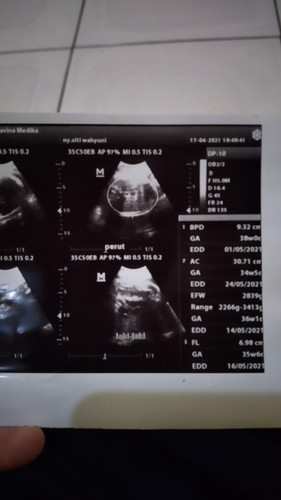

Assalamualaikum bunda,mohon di jawab ya pertanyaan sayaaaya hamil udah 40 minggu,tp belum ada tanda" keluar lendir kecoklatan cjma baru lendir biasa aja.. Kalo tanda" misal sakit selangkangan vagina sama kenceng perut bagian bawah udah sering..hpl tgl 16 mei tp aampe sekaeang belum lahiran.. Adakan bunda" yg mengalami juga??? Tolong banyu di jwb ya bunda#seriusnanya #bantusharing